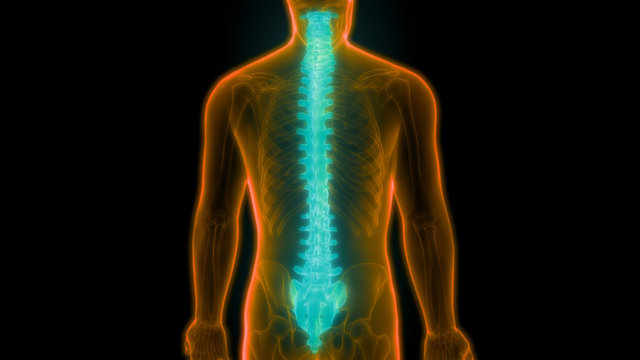

1- Kırık: Osteoporoz sonucunda üzerine yük binen kol veya bacaktaki uzun kemikler ile omurgayı oluşturan omur kemiklerinde çeşitli düzey ve şiddetlerde çatlama veya kırıklar meydana gelebilir.

2- Boyda kısalma: Omur kırığı sonrası omurganın kısalmasına bağlı olarak hastaların boyunda kısalma görülebilir.

3- Kamburluk: Omurların kırılması sonucu omurgada öne doğru eğilme görülebilir ve buna bağlı olarak değişik düzeylerde kamburlaşma ortaya çıkabilir.

6- Nörolojik bozukluklar: Omurga kırıklarının omurilik kanalına bası yaptığı durumlarda, uzuvlarda his veya güç kaybı ve idrar kaçırma gibi farklı düzeylerde sinir sistemi sorunları görülebilir.